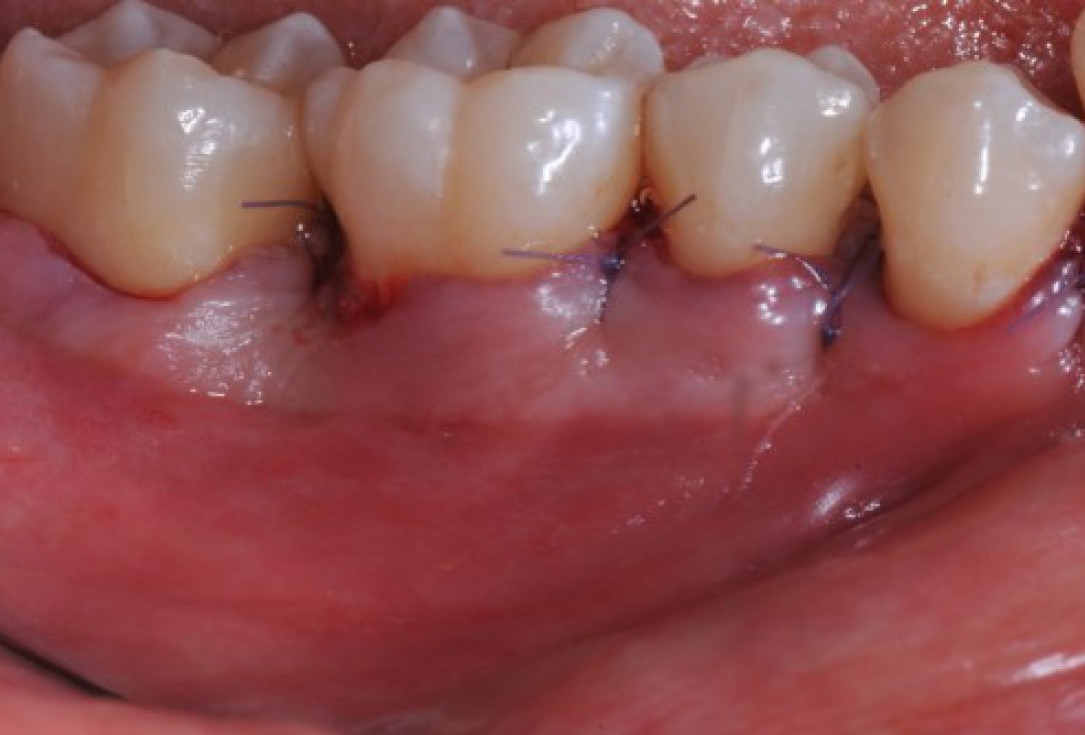

11/22 - Coronal advancement of the flap and suturing to achieve primary wound closure. Buccal view.

Deep intrabony defects treated using Straumann® Emdogain® - Dr. M. Stefanini